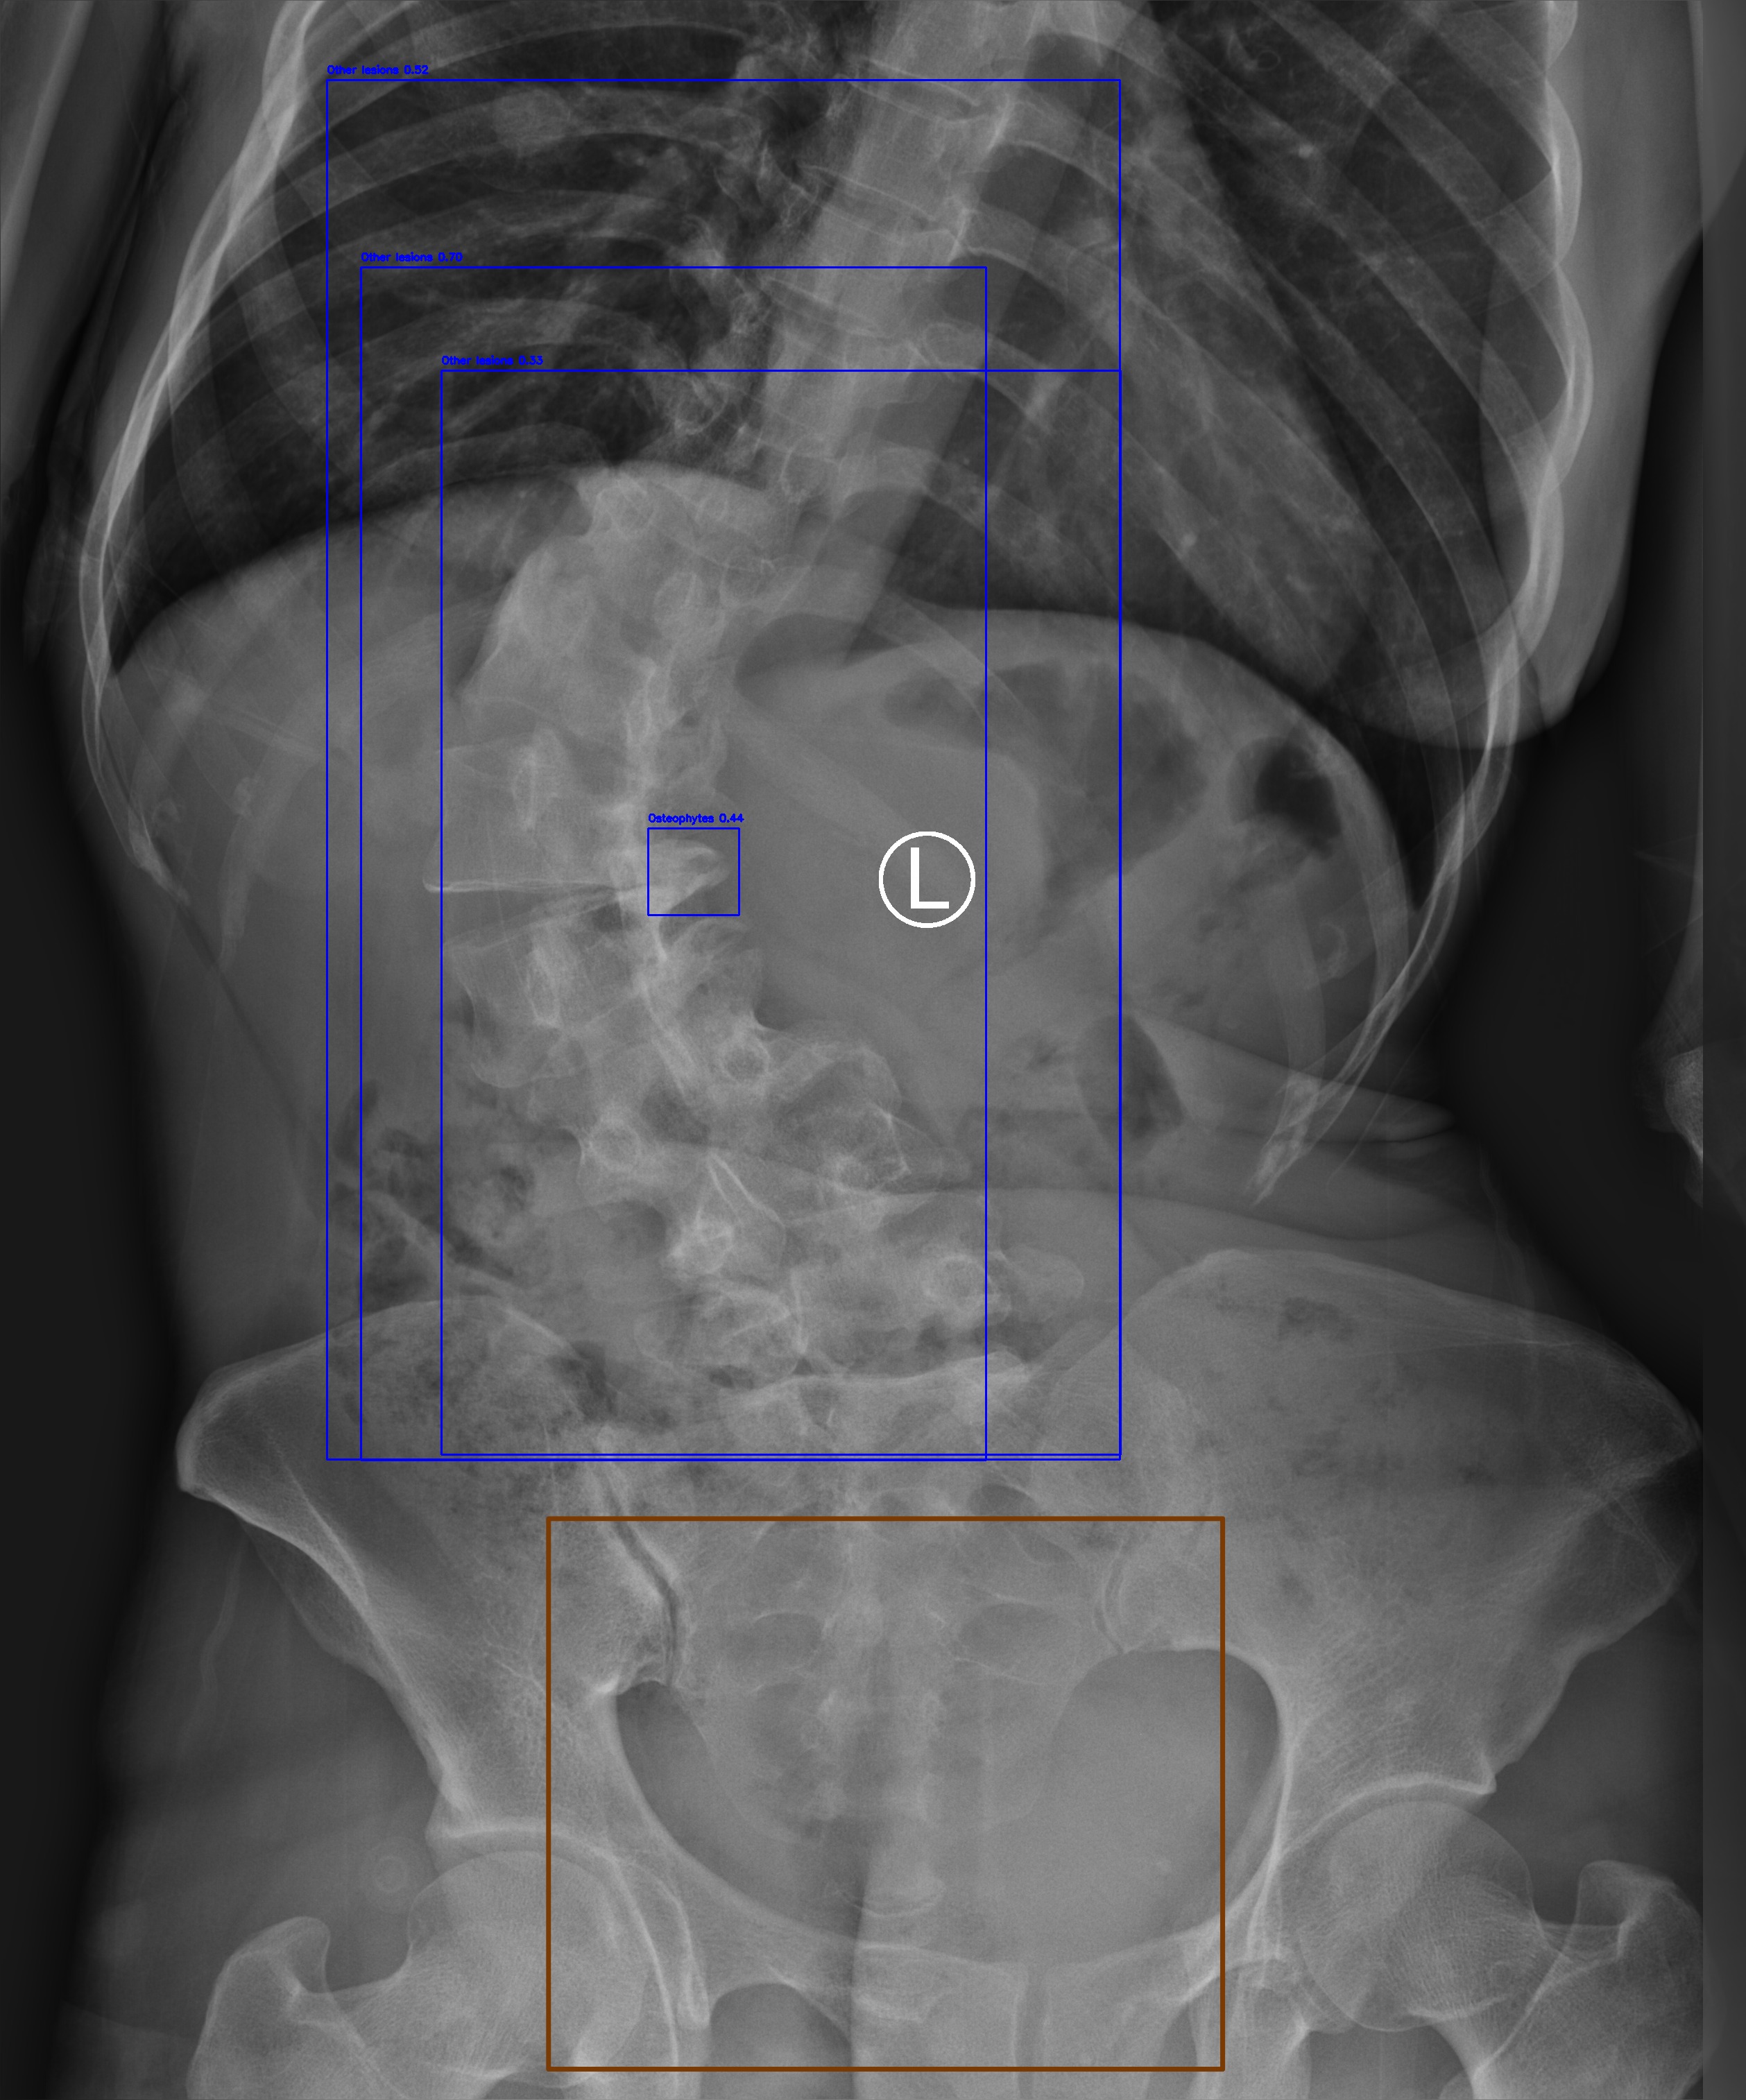

Osteophytes

(b) Osteophytes

Automated Lesion Detection and Localization: Visual demonstration of the cascaded DERNet-YOLO11 framework on VinDr-SpineXR benchmark images. The figure presents eight representative cases including seven pathological conditions with precise bounding-box localization: (a) Vertebral Collapse, (b) Osteophytes, (c) Spondylolisthesis, (d) Surgical Implants, (e) Disc Space Narrowing, (f) Foraminal Stenosis, (g) Other Lesions, alongside (h) a Normal spine radiograph for comparison. Each pathological case demonstrates the model's capability to accurately detect and spatially localize subtle lesions despite significant class imbalance (46.9:1 ratio), small object scales (often <1% of image area), and anatomical structure overlap. The localization boxes validate the clinical applicability of the integrated triage–localization pipeline.